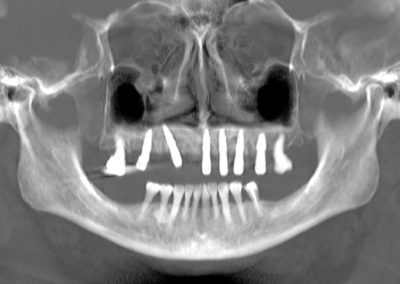

La intervención se realizó bajo anestesia general y contempló la extracción de la totalidad de los dientes del maxilar superior debido a una enfermedad periodontal avanzada, junto con la instalación simultánea de seis implantes dentales mediante cirugía guiada por planificación digital. En este caso, no se efectuó carga inmediata: el plan considera una carga temprana dentro del proceso de rehabilitación.

Uno de los aspectos más destacados fue que, en el mismo acto quirúrgico, se realizó la toma de la impresión para enviar a confeccionar una estructura provisoria completa (con la totalidad de los dientes maxilares), diseñada y elaborada mediante un proceso digital, lo que permite acortar tiempos y aumentar la precisión en etapas clave del tratamiento.